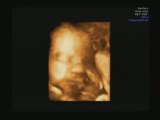

Mon échographie en 3D

ECHOGRAPHIE 3D 24 semaines

Echographie 3D